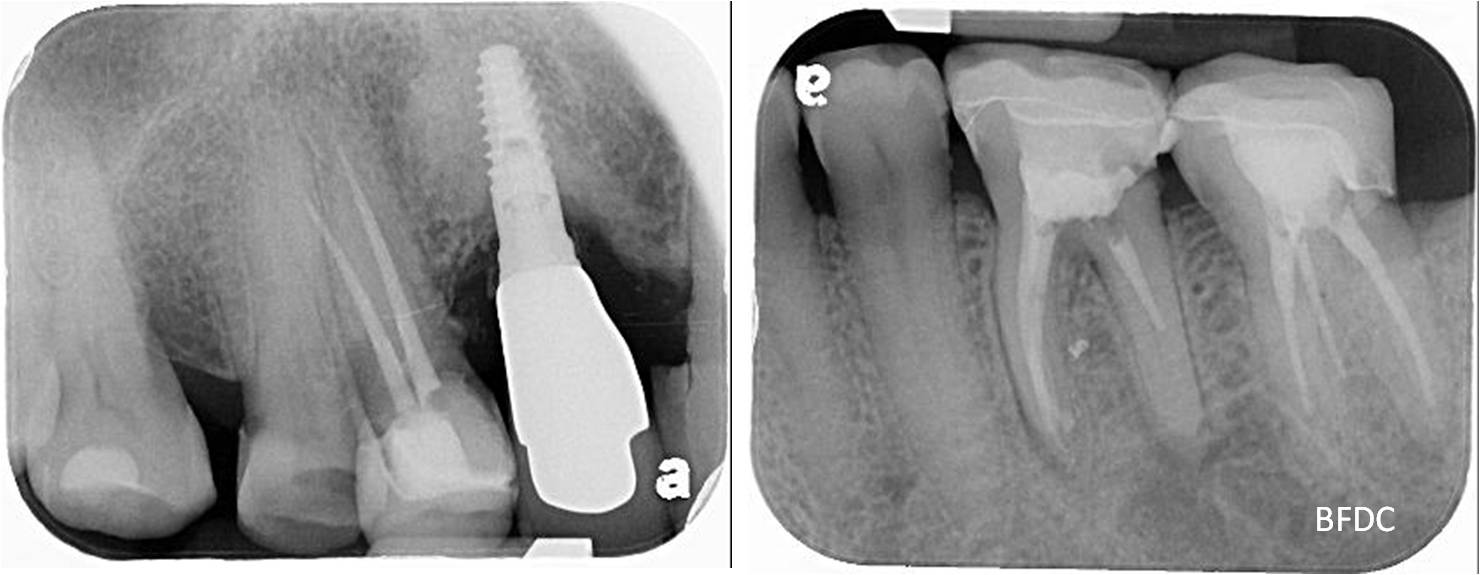

#37-顯微根管治療

治療後X光